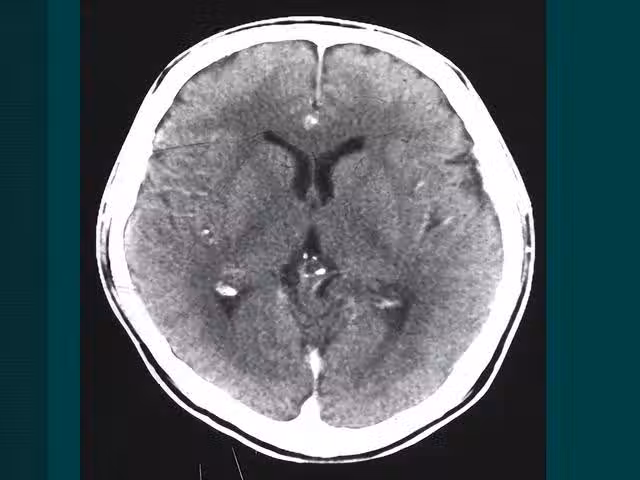

第②個:頭暈頭痛

很多人會把頭暈頭疼不當回事,但如果經常出現頭暈頭痛的症狀,就一定要小心,最好在醫生的指導下做一些詳細的檢查,看看病因,如果確定是腦部引起的,要儘快治療。

腦部血管破裂不是一下子發生的,是血管中的血栓慢慢形成的過程,而在血栓慢慢形成的過程中,腦部血液流通受阻,血管擴張,擴張後的血管慢慢擠壓到了周圍的組織,就會引起頭暈頭痛的症狀。